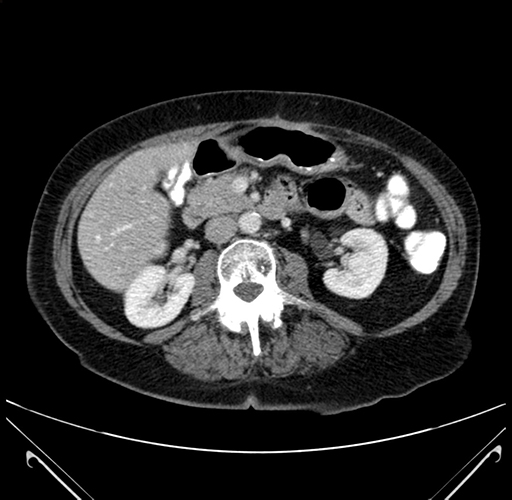

Axial Venous